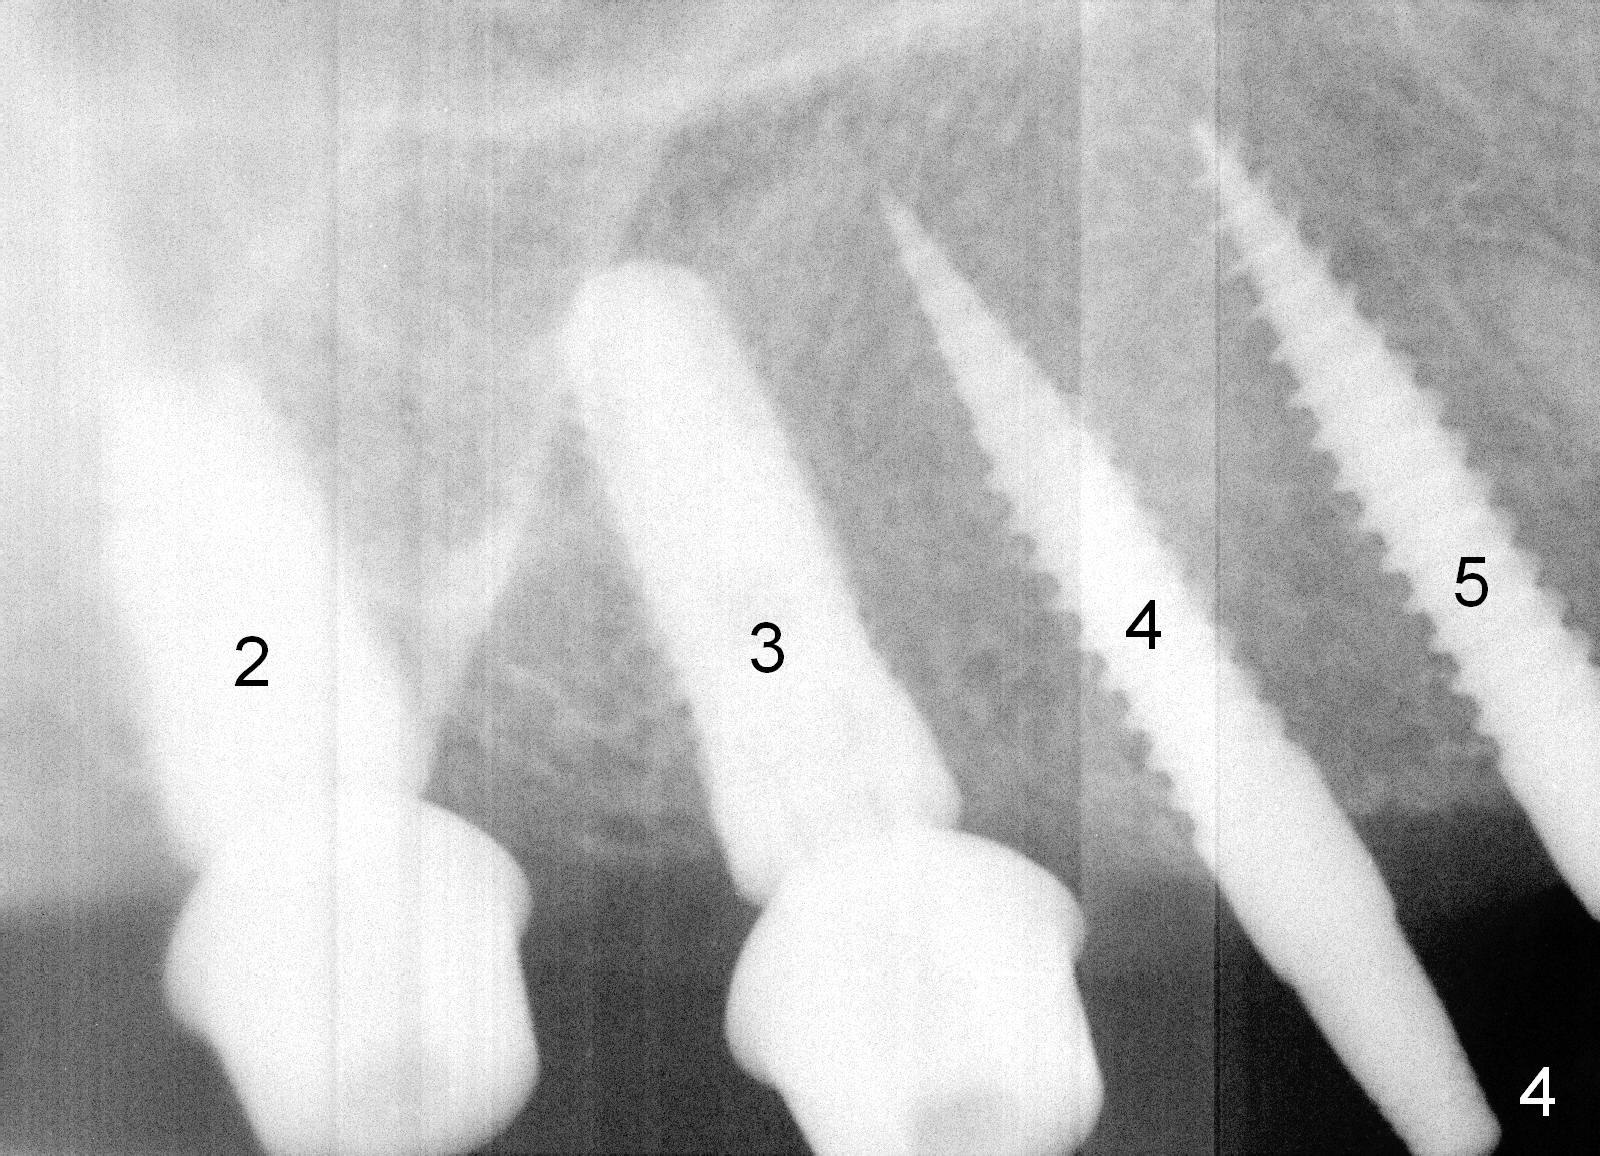

Osteotomy in the upper posteriors starts through a surgical stent for 12 mm. After incision, each osteotomy is examined, adjusted and extended 2 mm shy of intended (Fig.1,2). It appears that the trajectories at #4,5 are off (Fig.2). After re-adjustment, the trajectories are acceptable (Fig.3 (red dashed line; part of the root of the tooth #6)). Four implants are placed basically in accordance with the plan: 5.9x10 mm at #2, 5x14 at 3, and 3x14 mm 1-piece at 4 and 5 (Fig.4,5). Fig.6 shows the narrow ridge at #4 and 5 after implant placement. Although abutments are placed at #2 and 3, an immediate provisional bridge cannot be fabricated because of lack of enough clearance (supraeruption of the opposing dentition).